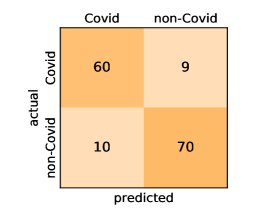

Here, we present and discuss the obtained results for detecting COVID-19 on the considered CT image datasets with different deep networks. We report the quantitative results along with the confusion matrices for every single architecture of the adopted networks.

On the COVID19-CT dataset, the overall performance with respect to all evaluation metrics is inferior to that on the SARS-CoV-2 dataset. This can be attributed to the cross-source heterogeneity of the CT images in the dataset. The Non-COVID-19 CT images were taken from different sources and show diverse findings which pose difficulty to distinguish between COVID-19 and other findings associated with lung diseases due to the potential overlap of visual manifestations (see Figure 8). Another reason is that, the CT images in the COVID19-CT dataset show strong variations in contrast, variable spatial resolution and other visual characteristics, which could affect the model’s ability to extract more discriminative and generalizable features.

It is also worthy mentioning that for the COVID19-CT dataset the inter-fold variations grow substantially due to the small size of the dataset. During 5-fold cross-validation the training set consists of about 600 images only and the test fold has less than 200 images, which has to produce statistical fluctuations. Metrics considering the overall performance like the accuracy have less inter-fold variation. However, we observe stronger variations in metrics, that test the bias towards one of the classes like the specificity. The standard deviation of the specificity indicates that the different folds tend to encourage the model to focus more on COVID or more on Non-COVID cases. This phenomenon occurs even for stratified 5-fold cross-validation, where the distribution of classes in each fold represents the class distribution of the entire dataset, and it seems to originate from the small number of images only.

Our models achieve fairly good performance compared with the recently published work using the exact network architectures. This can bet attributed to a better optimization of our models and the effectiveness of our fine-tuning strategy using custom-sized inputs determined specifically for each architecture. Here, we see that DenseNet201 outperforms all other architectures. The model achieves average accuracy and sensitivity scores of and , respectively. It also identifies all COVID-19 images with only four images, on the average, are falsely predicted as Non-COVID-19. DenseNet169 achieves the second best average accuracy of and a very high sensitivity identical to the best model. The DenseNet121 and Xception models have nearly identical results for all evaluation metrics. We observe that small-sized networks such as ResNet18 achieves comparable results with other deeper models. The SqueezeNet and ShuffleNet models perform at a similar level of accuracy. The variants of the ResNeXt models have comparable results and perform as good as the different ResNet variants. A detailed analysis on the class-wise results for individual models is presented in the confusion matrices in Figure 10.